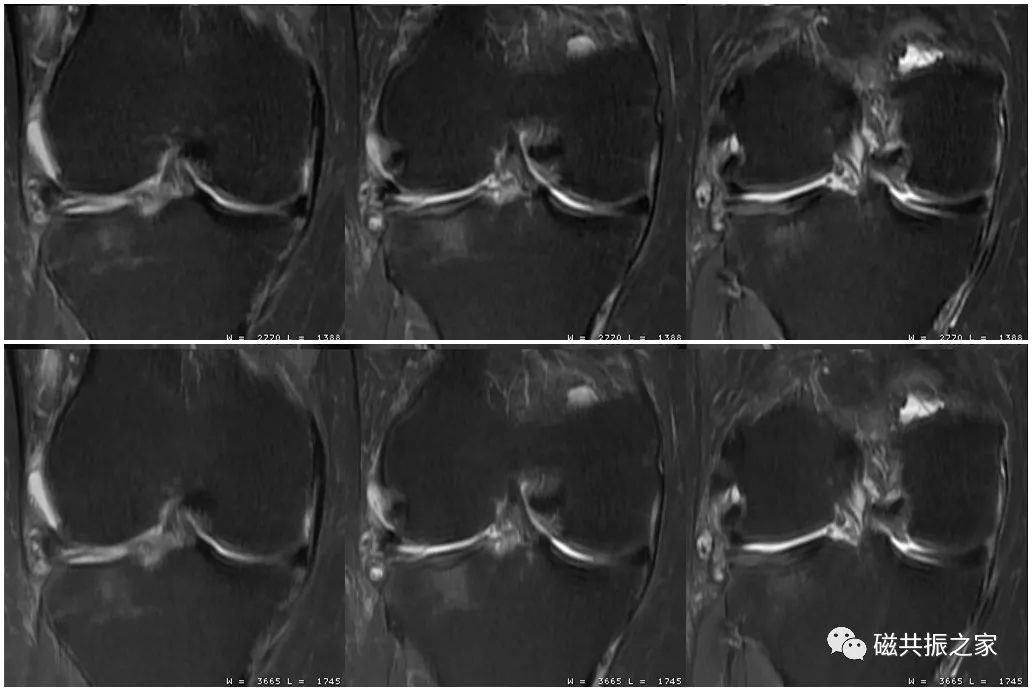

如图,上1,2,3幅图像的频率编码数为320;下1,2,3幅图像的频率编码数为512;虽然下面三幅图像的扫描体素较上面三幅图像更小,但其分辨率不及上面三幅图像。图像的分辨率并不是由单一参数决定的,在调整参数时应综合考虑时间、信噪比、对比度、伪影等相关因素。